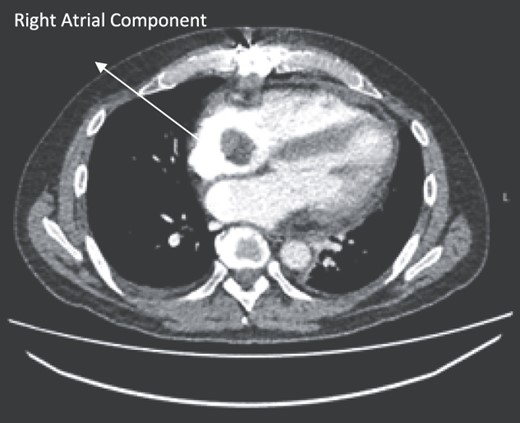

A 52-year-old gentleman was admitted to a district general hospital for shortness of breath causing type 1 respiratory failure with oxygen saturations of <90% despite high flow oxygen. His past medical history was unremarkable, and he was usually fit and well. A CT Pulmonary Angiogram (CTPA) was undertaken, which showed a heterogeneous oval-shaped lesion measuring 15 × 9 × 14 cm3 between the heart and the diaphragm, with a median attenuation of 35 HU and no enhancement during the arterial phase. Further solid lesions of 14 mm in the right lower lobe and 5 mm in the right upper lobe raised the suspicion of a primary cardiac sarcoma with pulmonary metastasis. This is shown in Fig. 1. Subsequent urgent CT staging (Fig. 2) was undertaken, which confirmed an indeterminate space occupying the inferior pericardial space, right atrial (RA) filling defect and anterior nodular pericardial thickening. No intra-abdominal or bone lesions were identified. An echocardiogram also confirmed these finding with the addition of no flow through the tricuspid valve (TV), as shown in Fig. 3.

CTPA showing oval-shaped heterogenous lesion as well as RA filling defect.

CT thorax-abdomen pelvis, depicting the RA filling defect as well as pericardial bulk.